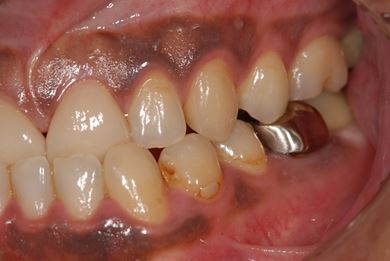

性別/年齢 男性 / 39歳

主訴 前歯のすき間を治したい。

治療方針 上顎前歯をオールセラミッククラウンにて審美的回復を行う。

治療内容 CAD/CAMオールセラミッククラウン2本

治療前

• 治療前